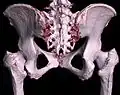

-

3D-Rekonstruktion (Volumenrendering) des Beckens aus einem CT-Scan -